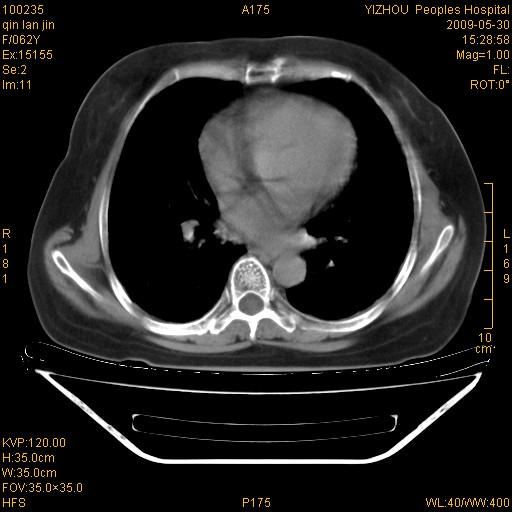

弥漫性双肺间质纤维化。

两肺弥漫性间质性病变(间质性肺炎伴肺间质纤维化?)。

弥漫性双肺间质纤维化

支持弥漫性肺间质纤维化。

支持 特发性间质性肺炎【iip 】

间质性肺炎伴肺间质纤维化。

纵隔淋巴结大,须排外癌性淋巴管炎